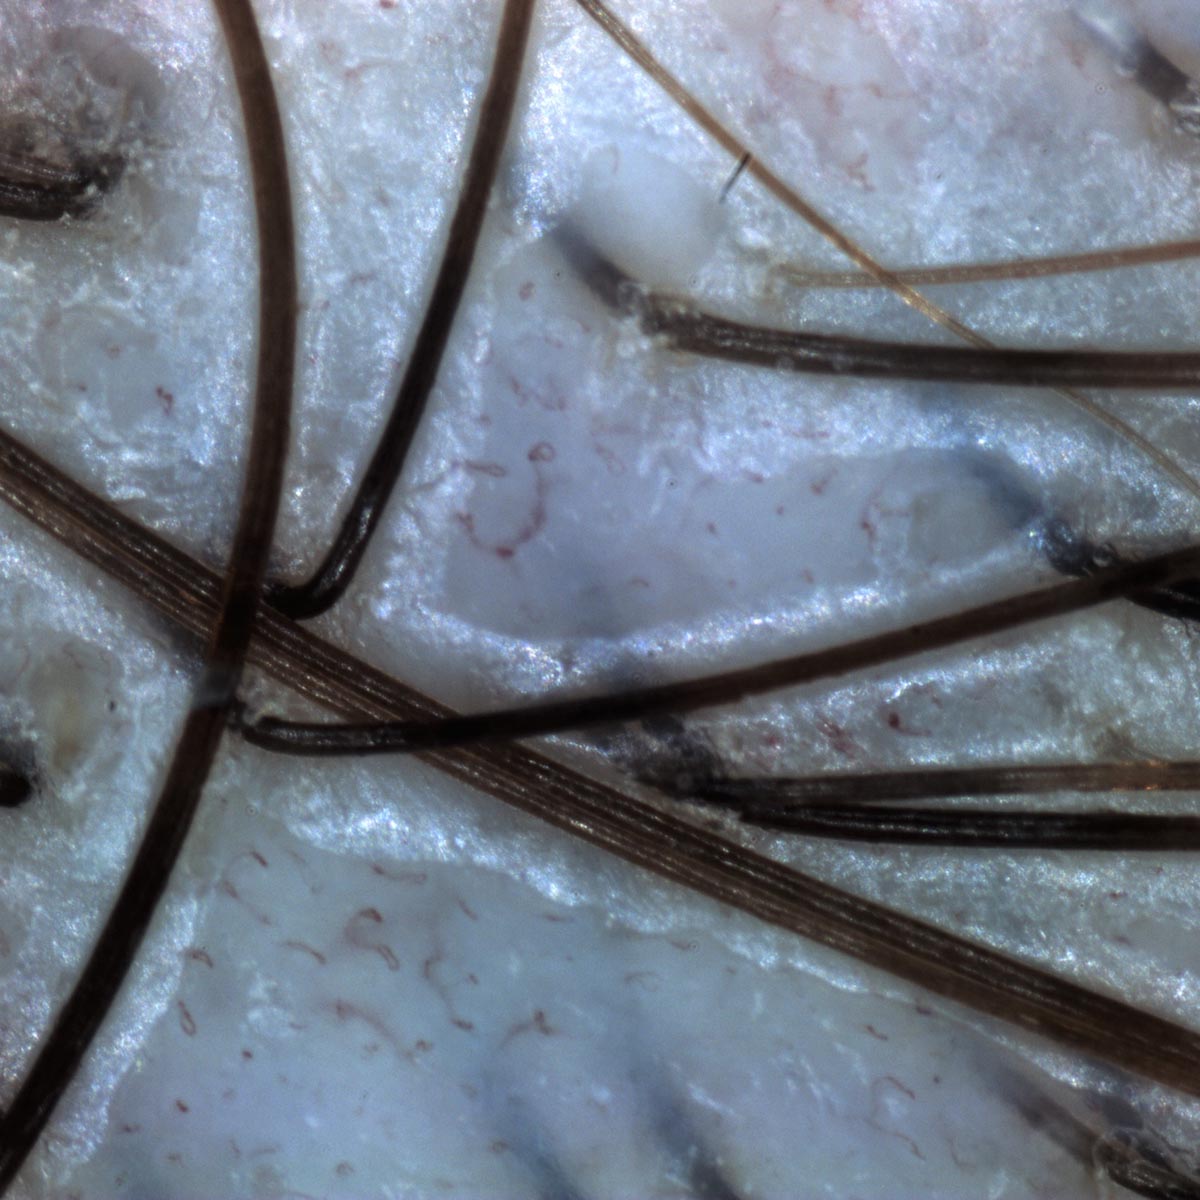

Spesso le immagini dermoscopiche delle lesioni cutanee appaiono parzialmente coperte dai peli,il che rende la valutazione delle caratteristiche del neo più complicata per il clinico.

Una possibile soluzione è quella di tagliare o sradicare eventuali capelli presenti sulla lesione cutanea, ma questo non è sempre auspicabile.

Il software IRSkin offre una soluzione diversa, la funzione Razor, che tenta un’eliminazione algoritmica dei peli.

Prima di usare razor

Dopo aver usato razor